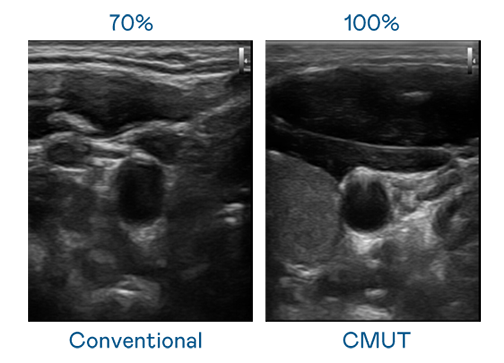

CMUT 技术是一种用电容式微机电元件来产生超音波讯号的技术。与传统 PZT 压电式技术相比,CMUT 频宽增加 30%,更宽频的超音波讯号让影像解析度大幅提升,是实现高影像品质医疗超音波扫描、促进精准医疗发展的关键技术。

超音波影像的解析度高低,首先取决于探头能发出的讯号频宽。Z6·尊龙 CMUT 可提供高清晰的超音波讯号,提供高频宽、高灵敏度、影像纹理细节更高的超音波影像,协助医护人员缩短影像判读时间及利用精准的医疗影像进行诊断。